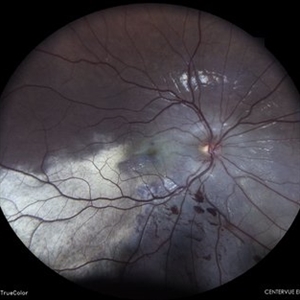

Coats' Disease Montage

Fundus photograph of a 5-year-old male child who presented with unilateral diminution of vision since one month.

Photographer: Dr. Nivesh Gupta, M.S., Retina Foundation, Ahmedabad

Condition/keywords: angiomatosis retinae, Coats' disease, exudative detachment, subretinal exudates